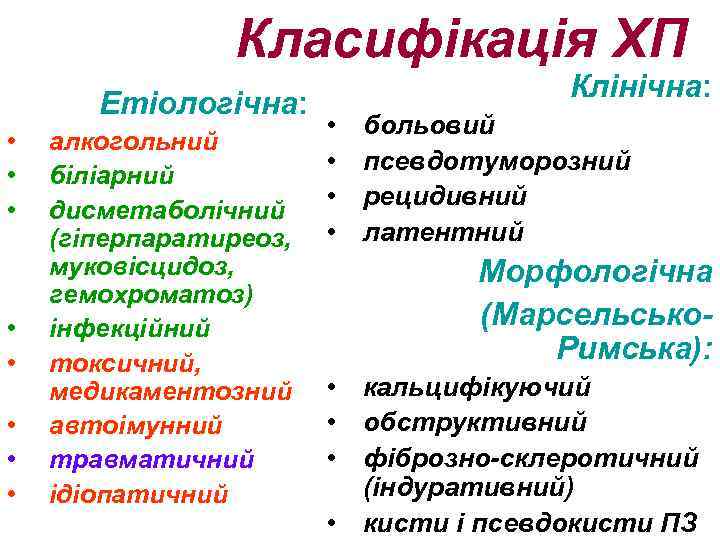

Класифікація ХП Етіологічна: • • алкогольний біліарний дисметаболічний (гіперпаратиреоз, муковісцидоз, гемохроматоз) інфекційний токсичний, медикаментозний автоімунний травматичний ідіопатичний Клінічна: • • больовий псевдотуморозний рецидивний латентний Морфологічна (Марсельсько. Римська): • кальцифікуючий • обструктивний • фіброзно-склеротичний (індуративний) • кисти і псевдокисти ПЗ

Класифікація ХП Етіологічна: • • алкогольний біліарний дисметаболічний (гіперпаратиреоз, муковісцидоз, гемохроматоз) інфекційний токсичний, медикаментозний автоімунний травматичний ідіопатичний Клінічна: • • больовий псевдотуморозний рецидивний латентний Морфологічна (Марсельсько. Римська): • кальцифікуючий • обструктивний • фіброзно-склеротичний (індуративний) • кисти і псевдокисти ПЗ